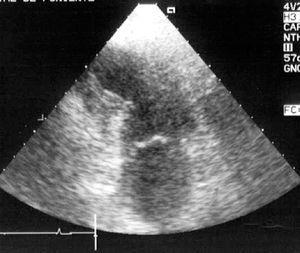

Aparte de la heterogeneidad de las distintas descripciones, de todos los estudios publicados se desprende que en presencia de patología neurológica grave se puede producir una disfunción miocárdica con una incidencia desconocida, pero que podría estar en torno al 9%, que mejora habitualmente en la primera semana, y es reversible en la mayoría de los supervivientes entre el primer y el sexto mes. Aunque la causa del fallecimiento es dependiente de la propia patología cerebral, dicha disfunción miocárdica reversible puede contribuir a la mortalidad, o al menos incrementar la morbilidad al poder cursar con complicaciones tales como arritmias potencialmente letales15,29, hipotensión arterial, edema pulmonar15,29, hipoxemia13-21, que podrían potenciar las lesiones cerebrales secundarias, así como formación de trombos intracavitarios en el ventrículo izquierdo12,14,15,18 que podrían provocar embolias15 (fig. 2). Por otra parte, esta disfunción miocárdica puede ser una causa directa del edema neurogénico o al menos contribuir a su desarrollo, ya sea por la propia disfunción ventricular sistólica o por otras complicaciones asociadas, tales como una insuficiencia mitral grave (figs. 3 y 4).

Figura 2. Ecocardiografía transtorácica, plano apical 4 cámaras, donde puede observarse una imagen de trombo y ecocontraste espontáneo en el ventrículo izquierdo de un paciente de 21 años con hemorragia subaracnoidea e hipoquinesia ventricular izquierda global grave.